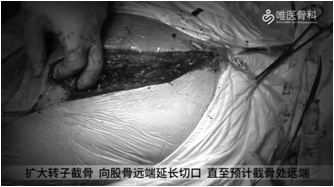

股骨侧制备(扩大转子截骨):取出近端骨水泥后,给予纵向劈裂髓腔内骨水泥,并尝试取出。本病例由于远端骨水泥清除困难,遂决定行扩大转子截骨(ETO),具体操作如下:

①给予向股骨远端延长切口,直至预计截骨处远端。显露股外侧肌后缘,在股骨粗线稍外侧纵行标记截骨线,验证远端截骨平面。